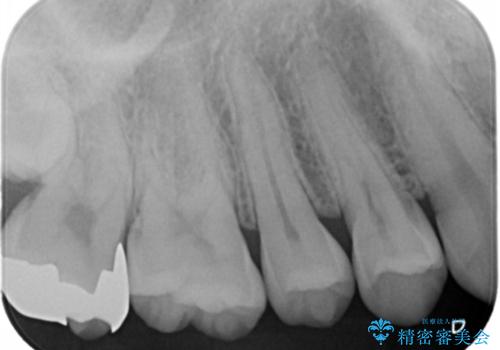

- 銀歯を白くしたいとのことで来院されました。

歯を覆っている銀の詰め物の面積が広く、セラミックで同じ形態にすると強度に不安が残るため被せ物での修復処置を行っていきます。

ブラッシングが上手な患者様であったため歯茎の締りもよく、大変適合の良い被せ物を装着することができました。